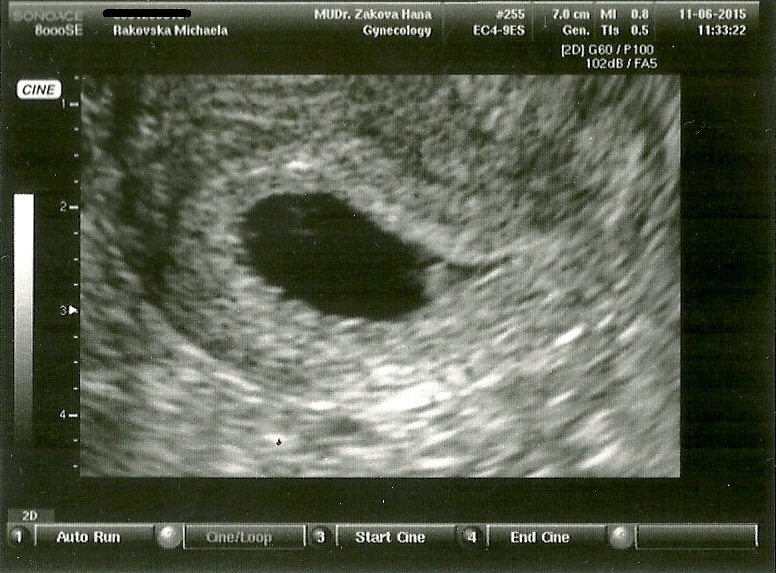

6tt, první kontrola na gynekologii :) Měříme 3mm a kousíček :P

Neeee nebylo vidět ještě vůbec nic 🙂 Mimuško mělo teprve 3mm 🙂